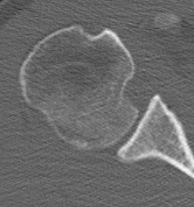

CT scan

Confirms dislocation

Reverse Hill Sachs

Humeral head defect

- caused by impaction of anterior humeral head on posterior glenoid

- intra-articular

- measured as a percentage of the articular surface